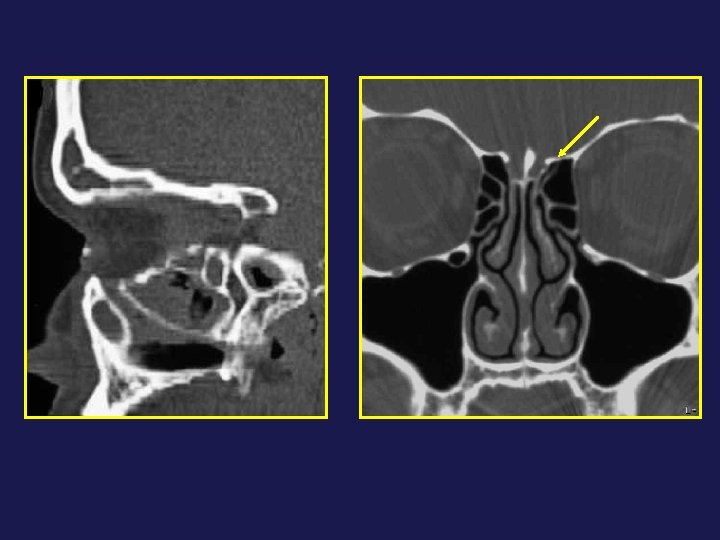

Cellule d’Onodi → Atteinte du nerf optique

→ Atteinte du nerf optique